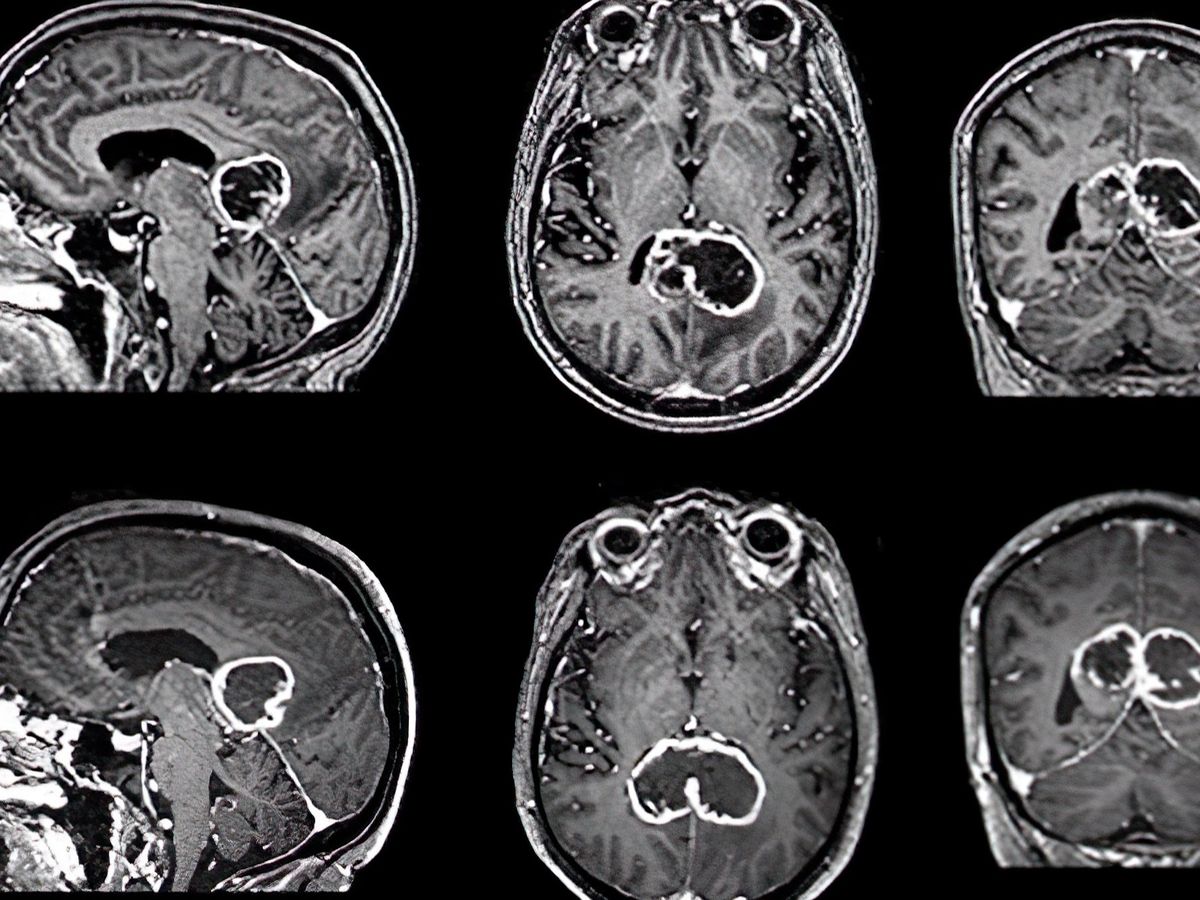

Meine Schwester Christine, 45, hat vor ein paar Tagen die herzzerreißende Diagnose eines unheilbaren Hirntumors erhalten (inoperables Glioblastom am Hirnstamm). Die Ärzte haben ihr nur noch wenige Wochen Lebenszeit prognostiziert.